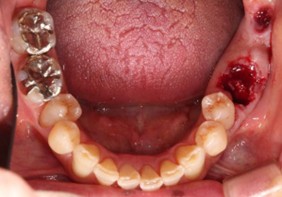

20代 男性

治療前

治療後

治療後- リスク・副作用

- 術後疼痛、歯肉腫脹

- 治療の費用

- 合計¥701,000(税込)

【内訳】

インプラント(1本)¥440,000

その他費用¥261,000

(薬・注射・レントゲン・CT・データ分析・骨造成・サージカルステント・血液検査・仮歯) - 年齢/性別

- 20代/男性

- 患者の具体的な症状

- 1年前に左上12 右上1の根の治療をし、その後放置していたら、左上2が破折した。

左上2インプラント補綴 左上1右上1オールセラミック装着。

歯根破折と虫歯による痛み、審美障害を主訴として来院。 - 検査方法

- コーンビームCT、レントゲン撮影

- 診断結果

- 左上2 歯根破折

- 治療詳細

- 左上抜歯後、インプラント埋入1本

骨造成あり 局所麻酔

インプラント治療後、左上1右上1セラミック修復2本 - 通院回数

- 9回

- 治療期間

- 12か月